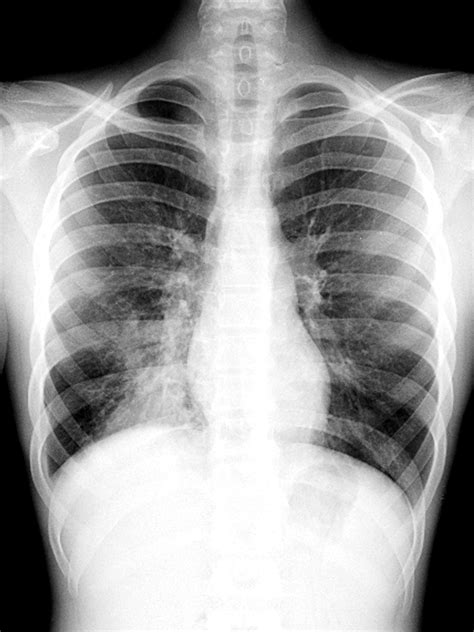

Healthy lungs appear mostly black on an X-ray because they are filled with air. When pneumonia is present, the areas of the lung affected by the infection appear as opaque, white, or cloudy patches. This phenomenon is known as consolidation. It occurs because the air in the alveoli has been displaced by fluid, inflammatory cells, or debris, which blocks the passage of X-rays.

The role of the Xray in pneumonia does not always end after the initial diagnosis. Physicians often order follow-up imaging to ensure that the lung tissue is healing correctly. This is particularly important for older adults, smokers, or those with underlying chronic lung conditions, as their risk of complications is higher.

Typically, a follow-up X-ray might be recommended to ensure that the consolidation has resolved, especially if the patient does not show clinical improvement after completing a course of antibiotics. In some instances, it is necessary to rule out an underlying mass or malignancy that might have predisposed the patient to recurrent pneumonia. Generally, it can take several weeks for radiological signs of pneumonia to disappear, even after the patient feels better, so follow-up imaging is not always necessary for everyone.